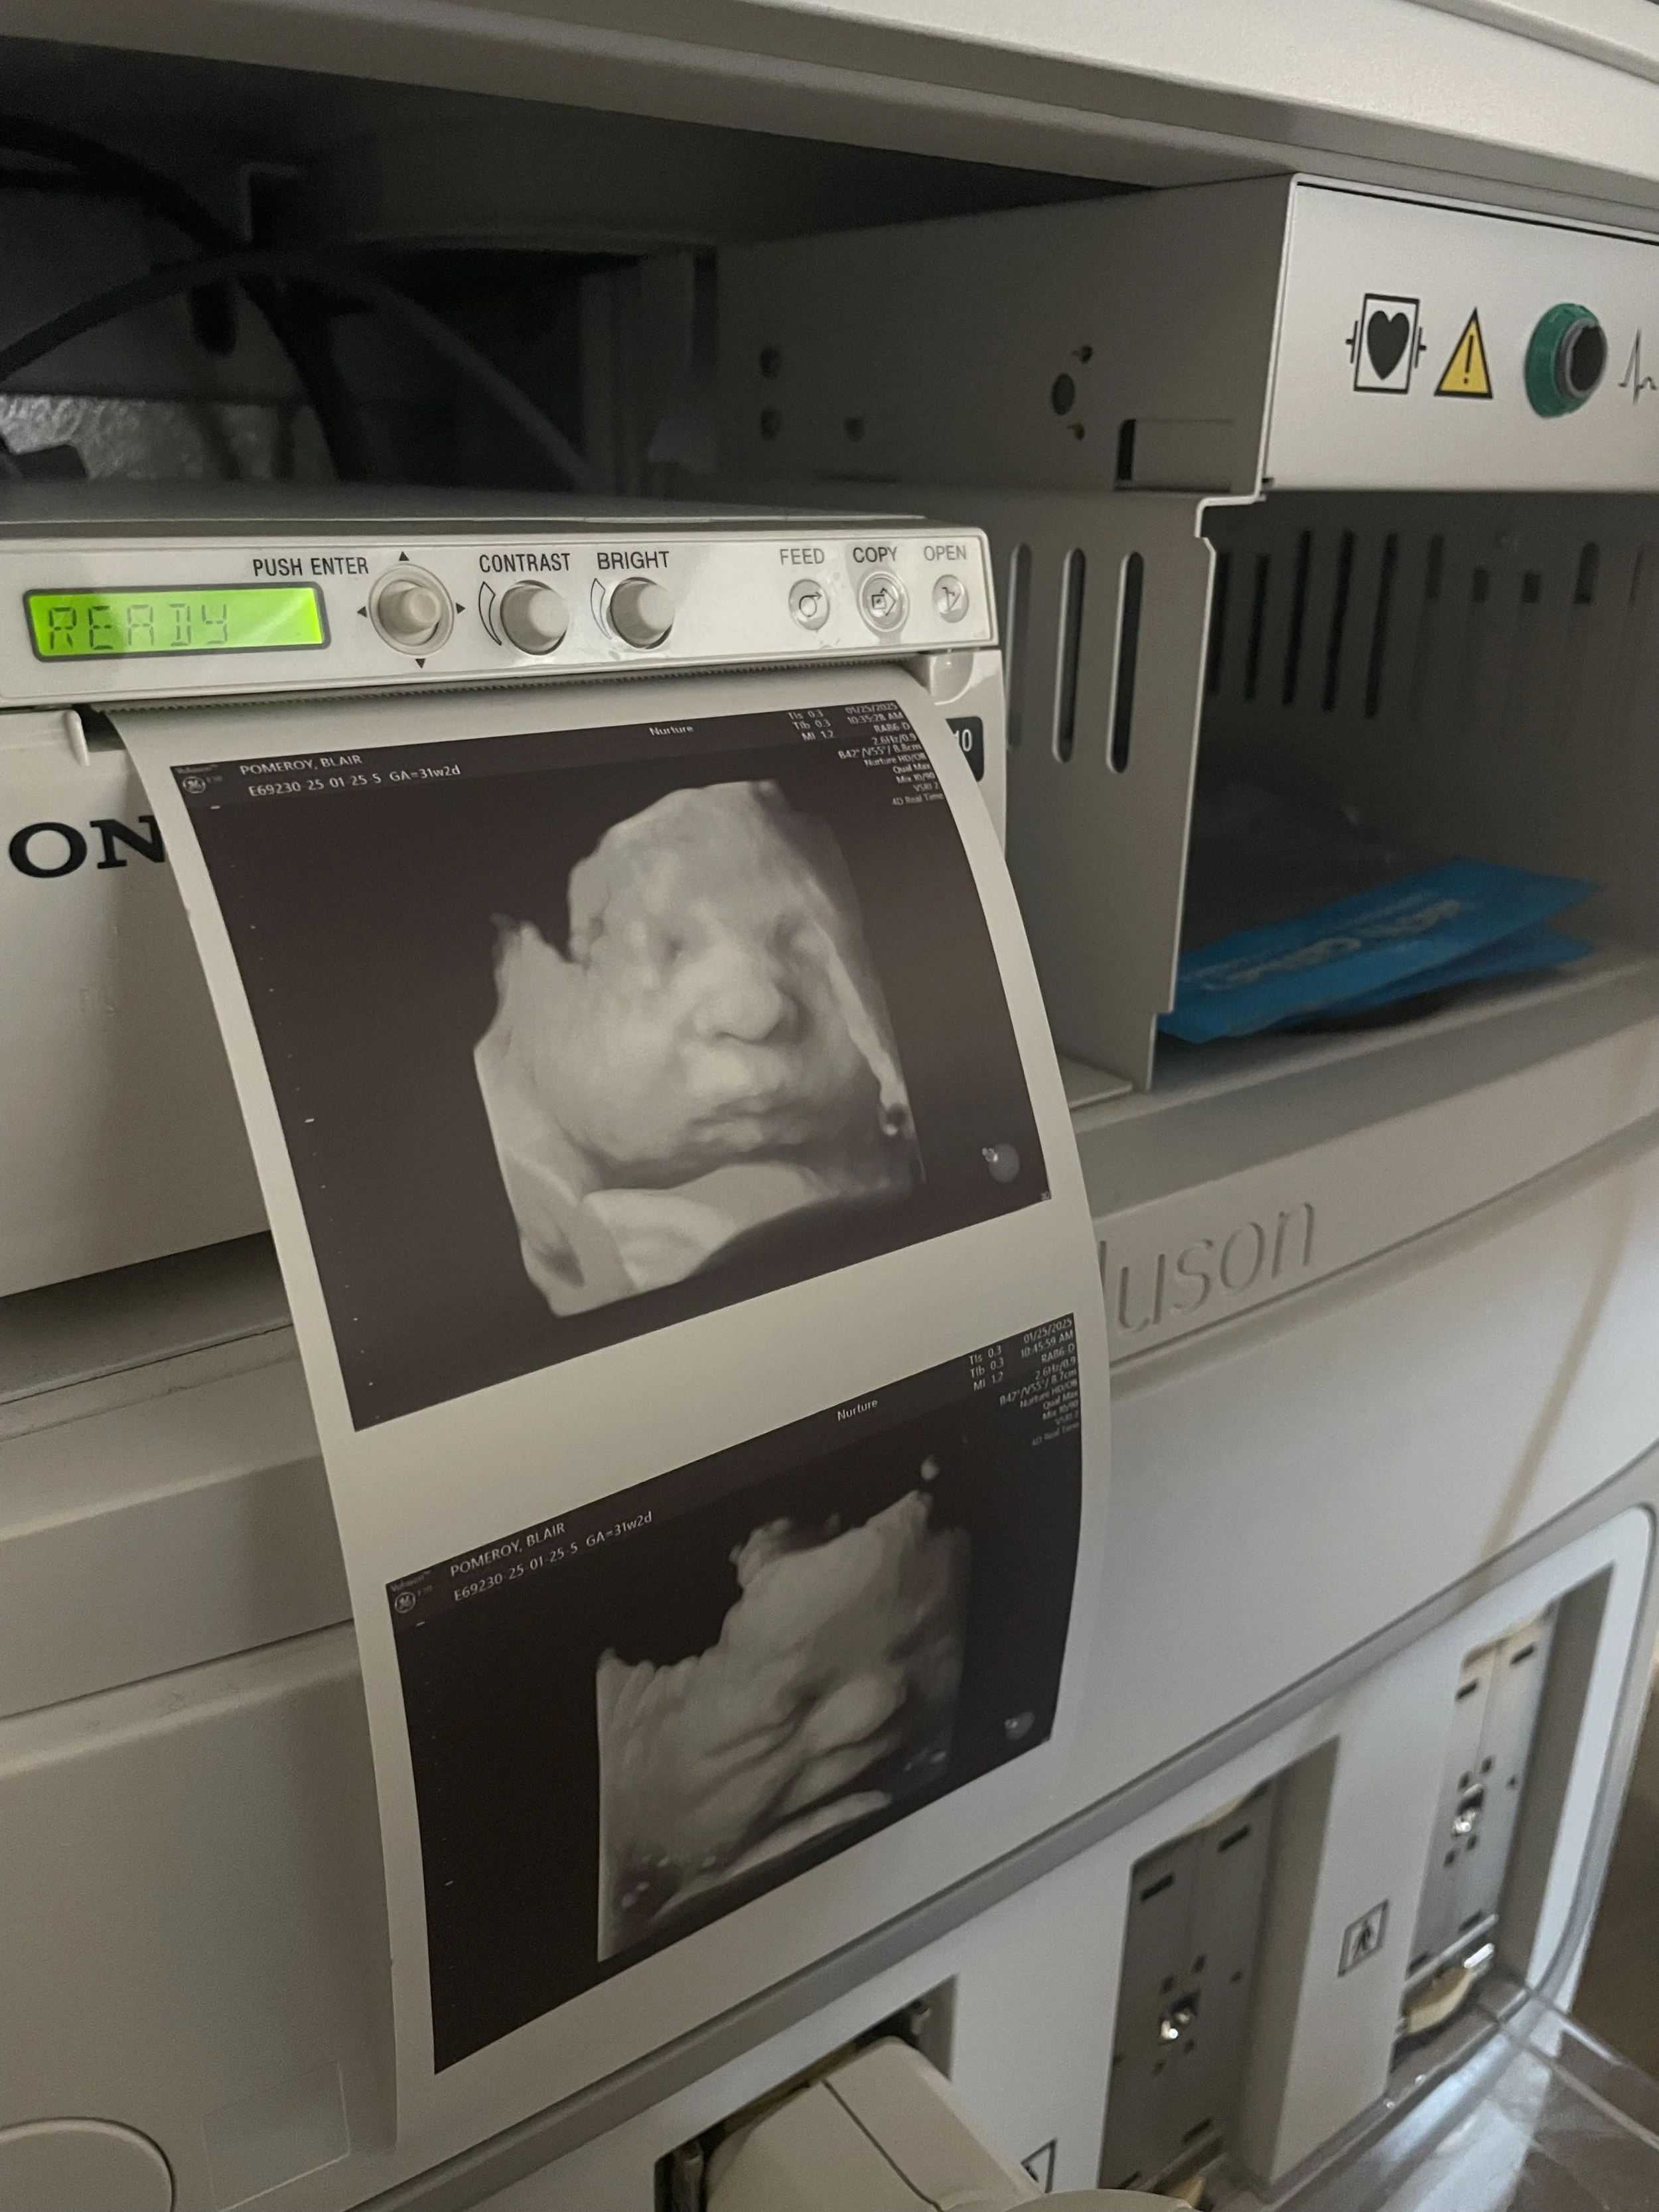

Seeing your baby suck their thumb, purse their little lips together, rub their eyes, and kick their little feet is magical.

Ultrasound image of a fetus inside the womb.

During your session, you’ll watch your baby in real time—seeing their movements, their expressions, their unique rhythms. These are moments of life in utero that are usually unseen, yet deeply felt. Many families describe it as the first time everything becomes real in a new way.

• 2D & 3D are still images, while 4D/HD adds the dimension of motion, so it looks like a video. HD is the newest fetal keepsake ultrasound technology on the market. HD allows you to see all the details of the baby by using software technology to change the focal points and "lighting" of the ultrasound.